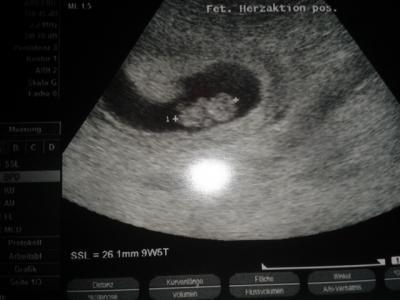

Alles super mit dem kleinen Zwerg. Schon fast 3 cm "groß" Hab auch ein Bild mitbekommen. Herz hab ich heute auch wieder schlagen hören Wahnsinn

Bild zu Mein Gummibärchen - Forum für August - Mamis